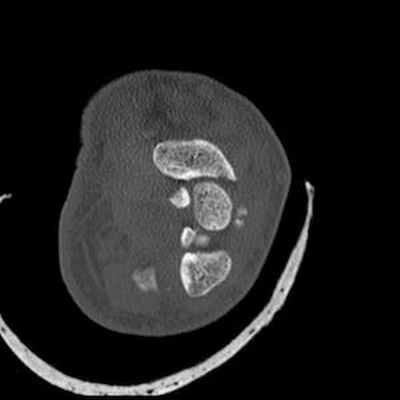

Трансладьевидно-перилунарный вывих запястья III-его типа

Трансладьевидно-перилунарный вывих запястья (перелом ладьевидной кости в виде основной сагиттальной линии, с образованием двух сильно смещенных фрагментов; проксимальный фрагмент остается в нормальном соотношении с полулунной костью; разъединение костей первого и второго ряда запястья).

Наличие мелких костных фрагментов вокруг трехгранной кости вместе с отрывными переломами; смещение кзади трехгранной кости.

Оскольчатый перелом шиловидного отростка лучевой кости.

Локтевая кость цела.